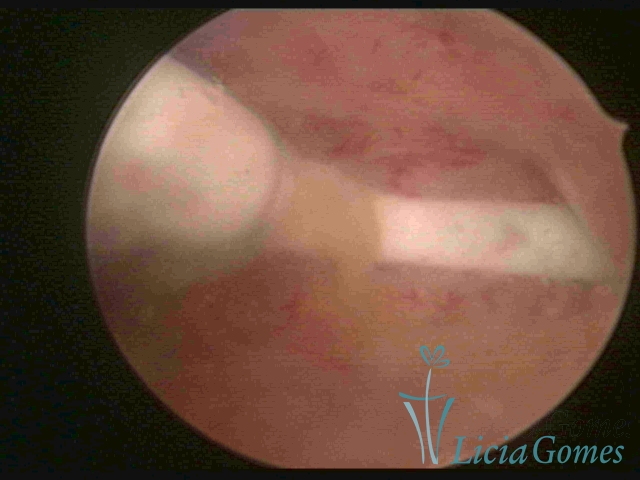

Normoinserted IUDo

Normoinserted IUD